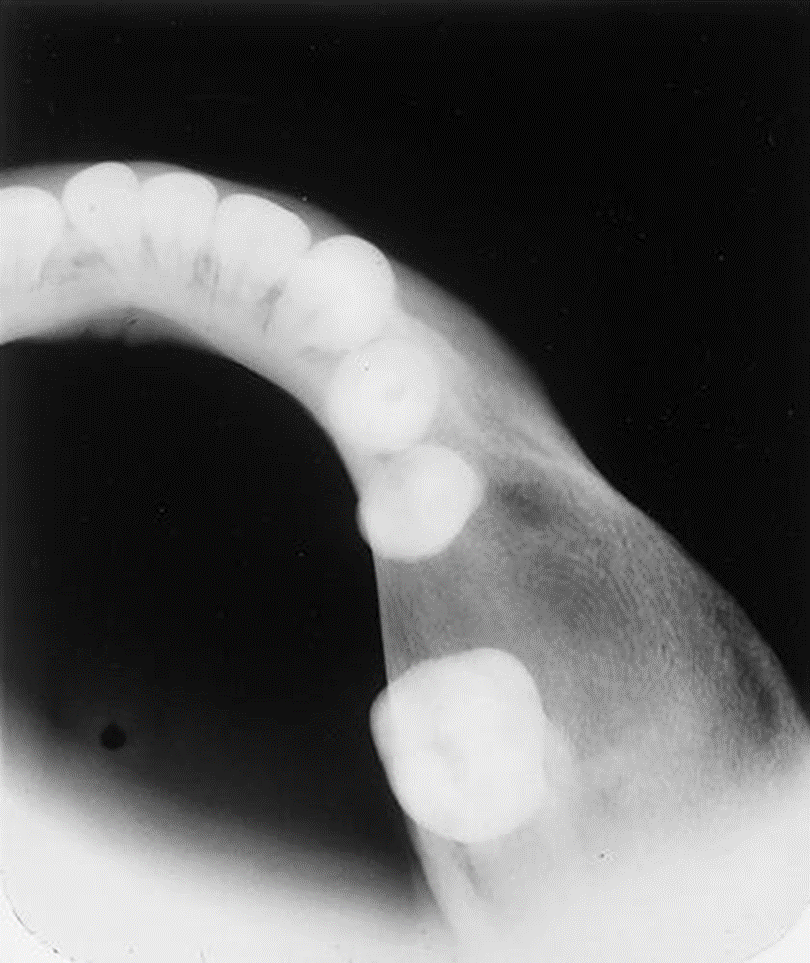

3. This is a 35-year-old asymptomatic woman who has slight buccal and palatal enlargement of the alveolar bone in this area. Other studies indicated portions of the zygoma were involved. This condition was first detected at age 19 years and is slowly progressive. Her alkaline phosphatase was normal to high-normal, and her serum calcium was normal.

What is your diagnostic impression?